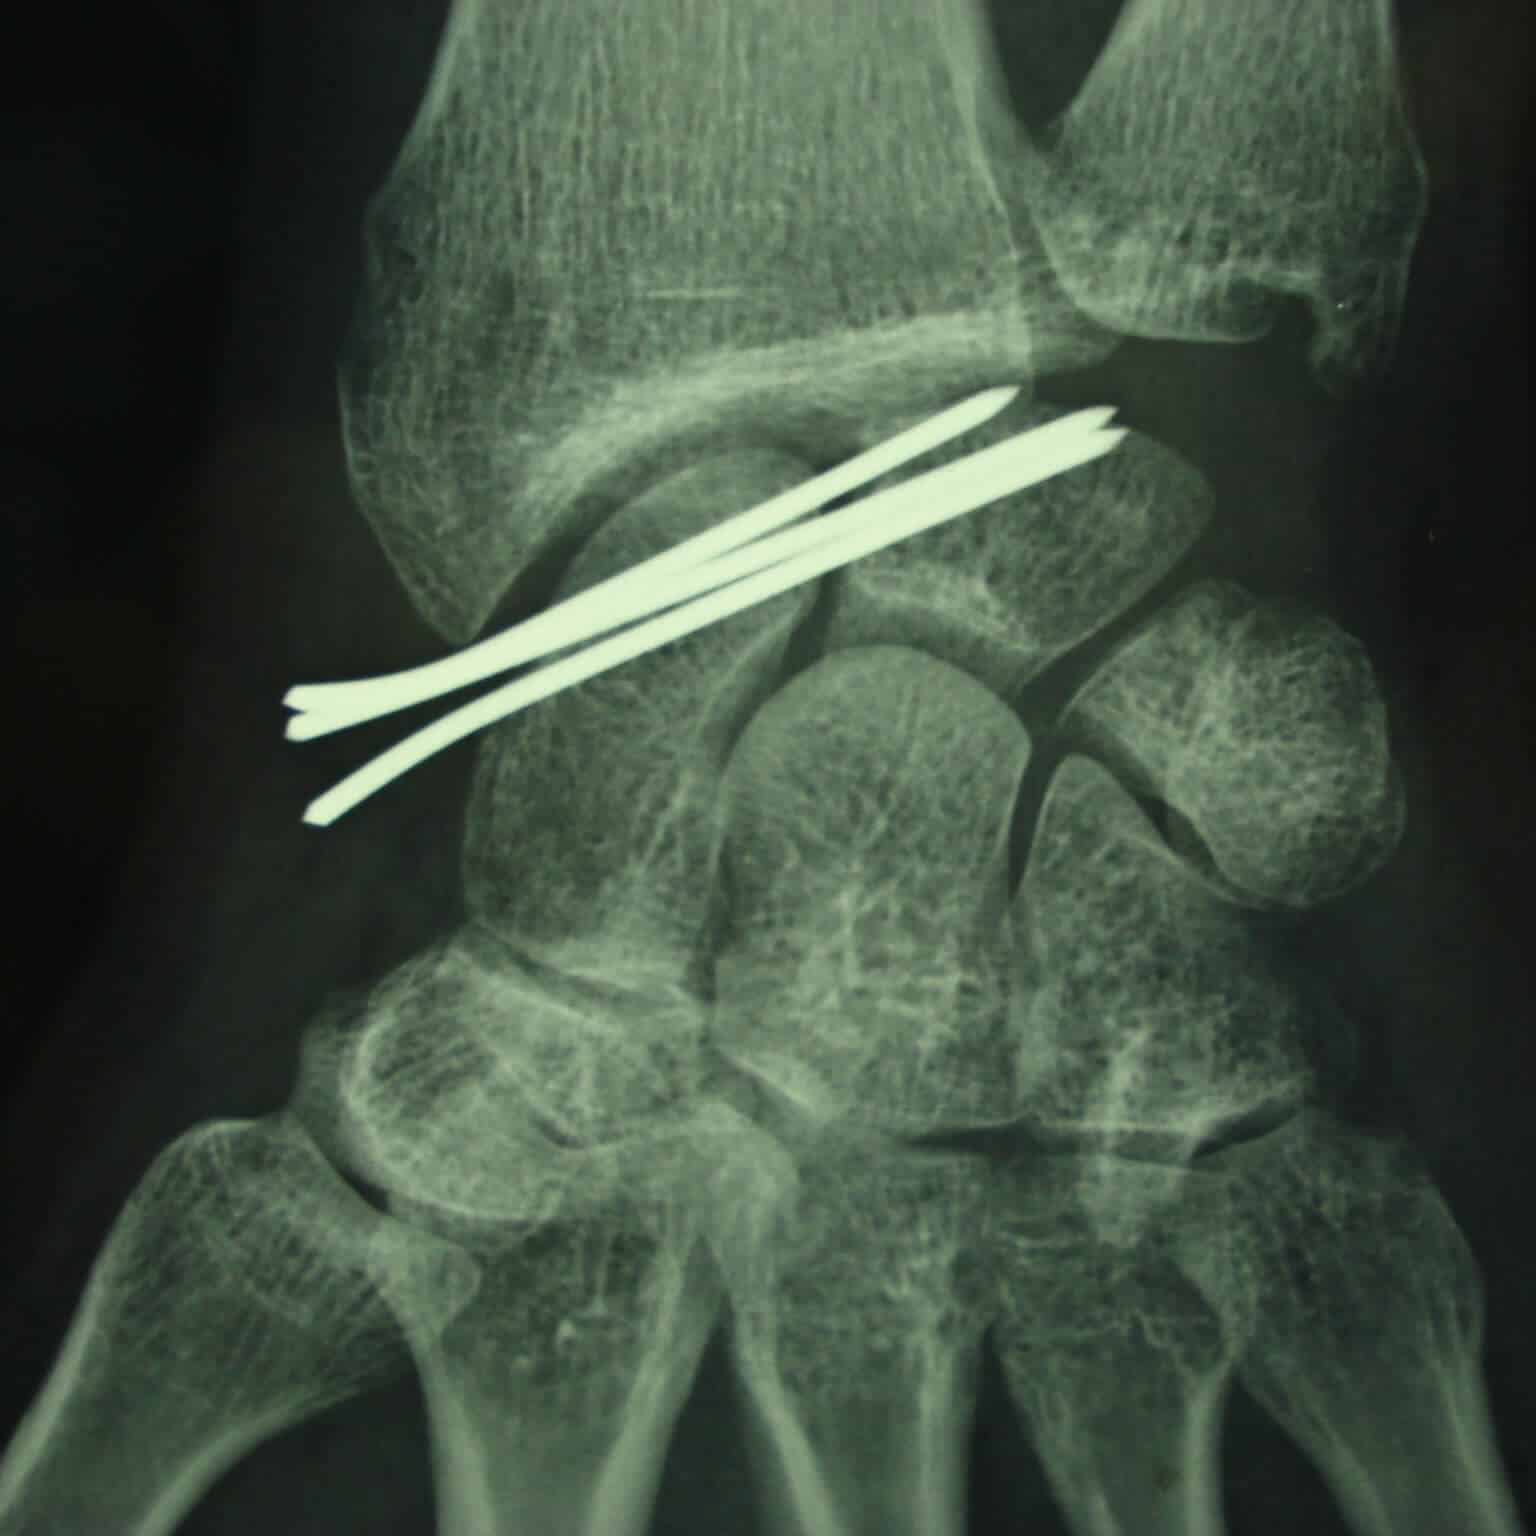

entorse ligament poignet rupture

Diastasis important par rupture ligamentaire complète du ligament scapho lunaire